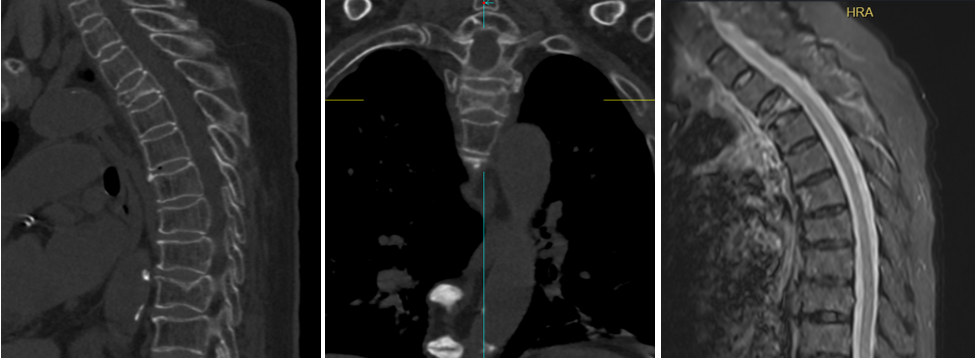

今年85岁的丁老太10天前在家里不小心摔了一跤,当即感到胸背疼痛不适,在家卧床休息数天仍不见好转。由于有过类似经历,丁老太之前摔跤后在当地医院做过椎体注射“骨水泥”的手术,且效果良好,于是家属想着大不了再打一次“骨水泥”就好了。随即到先前的医院检查,确诊是脊柱压缩性骨折,但与以往不同的是,这次是第三胸椎骨质疏松性压缩性骨折。第四胸椎以上由于位置特殊,手术操作难度大、风险高,通常是不做“骨水泥”手术的。当地医院的医生建议老太回家卧床休息保守治疗。随后患者和家属辗转就诊了几家医院,得到的建议都是保守治疗。难忍的疼痛及无法起床使老人陷入了绝望之中。

在多方打听后,抱着一线希望,丁老太家属带着患者来到了苏州大学附属独墅湖医院骨科姜为民主任的诊室。在充分了解丁老太的病情及诉求后,姜主任建议患者再次行椎体强化术。一家人经历了由绝望到希望的过程,但同时难免也有一丝担忧,因为此前的几位专家都告知他们无法手术。面对丁老太的难题,姜主任的自信不仅来自他多年积累的手术经验,还有我院新引进的第二代国产手术机器人的辅助。

丁老太入院第三天,姜主任在骨科主治医师蒋伟刚的配合下,成功为其实施了机器人辅助下经皮椎体球囊扩张成形术。术后第一天,患者可以下地活动,疼痛消失;第二天即出院,整个住院时间仅6天,真正做到了术后快速康复!丁老太的女儿感慨道,庆幸有独墅湖医院骨科姜主任和他的团队的出手相助,再加上手术机器人辅助,才帮助老人家过了这一关!